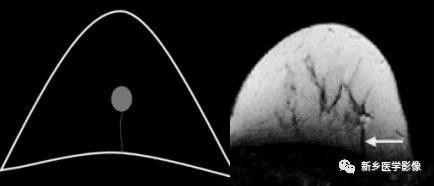

张力性纵隔气肿影像表现及严重度分级